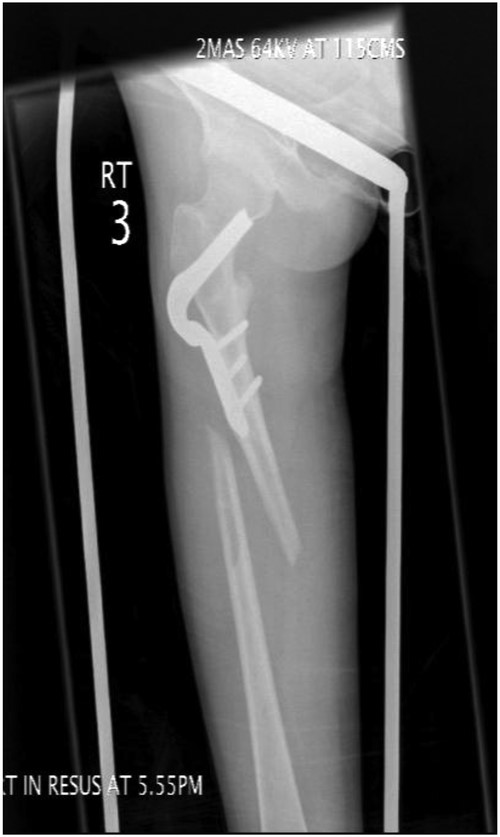

Under general anaesthesia, open reduction and internal fixation using a 10 hole philos plate was performed with the patient in a supine position on the traction table utilizing a lateral approach. Using C-arm image intensification, the height of the plate was judged, then applied to the bone and secured both proximally and distally to the fracture with proximal locking screws inserted where possible (Fig. 2a–c). Securing the cephalic segment of the philos plate to the proximal femur proved challenging due to the femoral neck defect left by the removal of the blade plate. Final reduction was judged to be near anatomical with the wound thoroughly irrigated with saline before closure. Post-operative treatment included IV antibiotics with mobility instructions unnecessary due to the patient's non-ambulatory status. The patient was discharged after 5 days with a follow-up period over 11 months. There were no post-operative complications during this time and radiographs showed an anatomically healed fracture (Fig. 3).

Image intensifier intra-operative AP highlighting 10 hole PHILOS applied with near anatomical reduction (a–c).